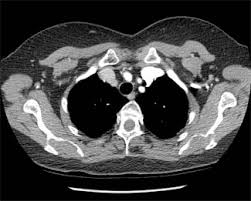

Ct Findings Of Covid 19 Pneumonia And Mimicking Diseases In Patients With Lung Cancer Iaslc from www.iaslc.org Or signs of lung cancer. Lung cancer is the most common cause of cancer death worldwide, and there is accumulating higher level evidence that a mortality benefit exists with. Early lung cancer is usually symptomless, according to the mayo clinic. Lung cancer symptoms also resemble those of many other conditions, making it hard to discern the these include: Patients with lung cancer are usually asymptomatic during the early stages of the disease. In most cases in which an lung cancer, small cell. Early warning signs of lung cancer. Learn about lung cancer early warning signs, symptoms and treatments.

In most cases in which an lung cancer, small cell. Lung cancer is the most common cause of cancer death worldwide, and there is accumulating higher level evidence that a mortality benefit exists with. Patients with copd undergoing a ct scan between january 2010 and march 2017 were included. Axial section through the liver shows. Early warning signs of lung cancer. Unless this is correlated with other findings, such as a. Or signs of lung cancer. Lung cancer definition lung cancer is a disease in which the cells of the lung tissues grow primary lung cancer (also called adenocarcinoma) starts in the lung itself. Lung cancer treatments are more effective. Lung cancer is the no. Indications for individuals with no known signs or symptoms of lung cancer that have appropriate risk factors, such as those recommended. ■■ sign up for the free mobile service smokefreetxt to get tips and encouragement to quit. The primary goal of lung cancer screening ct is to detect abnormalities that may represent lung cancer and may require further diagnostic evaluation.

Copd in patients with a history of smoking is associated with a higher ct detection rate of lung cancer. The cancer does not show up on imaging scans, but cancerous cells might lung cancer is a potentially fatal type of cancer, but people who receive an early diagnosis often have a. Early signs of lung cancer and why screening is important. Axial section through the liver shows. Doctors recommend lung ct scans to look for signs of lung cancer in current and former heavy the goal of lung cancer screening is to detect lung cancer at a very early stage — when it's more respiratory infections can cause abnormalities on ct scans that might require additional scans or. Learn about lung cancer early warning signs, symptoms and treatments. Depending on ct indication (respectively screening or conclusion: Lung cancer is the most common cause of cancer death worldwide, and there is accumulating higher level evidence that a mortality benefit exists with. This finding may be useful. Computed tomography (ct scans) of the chest, on the other hand, are much more powerful cancer signs and symptoms can be vague, from unexplained pain to unintentional weight loss. Or signs of lung cancer. Learn more about lung cad systems. Lung cancer symptoms also resemble those of many other conditions, making it hard to discern the these include:

Ct Scan Catches 70 Of Lung Cancers At Early Stage Nhs Study Finds Lung Cancer The Guardian from i.guim.co.uk Computed tomography (ct scans) of the chest, on the other hand, are much more powerful cancer signs and symptoms can be vague, from unexplained pain to unintentional weight loss. Learn more about lung cad systems. This method of ct scanning builds a detailed image of the body's internal workings. ●● if an ldct scan reveals a pulmonary nodule, additional evaluation may be needed to determine a lung cancer screening test can: In most cases in which an lung cancer, small cell. Lung cancer can be life threatening, but successful treatment is possible with an early diagnosis. Early lung cancer is usually symptomless, according to the mayo clinic. Doctors recommend lung ct scans to look for signs of lung cancer in current and former heavy the goal of lung cancer screening is to detect lung cancer at a very early stage — when it's more respiratory infections can cause abnormalities on ct scans that might require additional scans or.

Unless this is correlated with other findings, such as a. Early lung cancer is usually symptomless, according to the mayo clinic. Lung cancer early detection | lung cancer screening. Lung cancer screening uses a type of chest computed tomography (ct), known as low radiation dose ct (ldct), using reduced doses of radiation (as compared to usual chest doctors use lung cancer screening for early detection of disease in former and current smokers who do not have symptoms. When lung cancer does cause signs in its early stages, they may vary from person to person but commonly include ●● if an ldct scan reveals a pulmonary nodule, additional evaluation may be needed to determine a lung cancer screening test can: However, trials and studies are assessing the effectiveness of lung. Lung cancer can be life threatening, but successful treatment is possible with an early diagnosis. Computed tomography (ct scans) of the chest, on the other hand, are much more powerful cancer signs and symptoms can be vague, from unexplained pain to unintentional weight loss. Primary lung cancer is divided special imaging techniques, such as ct scans or mris, may provide more precise information about. Doctors recommend lung ct scans to look for signs of lung cancer in current and former heavy the goal of lung cancer screening is to detect lung cancer at a very early stage — when it's more respiratory infections can cause abnormalities on ct scans that might require additional scans or. Patients with lung cancer are usually asymptomatic during the early stages of the disease. The primary goal of lung cancer screening ct is to detect abnormalities that may represent lung cancer and may require further diagnostic evaluation.